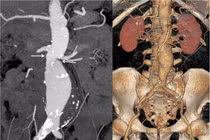

Can thiệp đặt stent, cứu bệnh nhân nhồi máu cơ tim sau phẫu thuật nội soi

Nhồi máu cơ tim cấp là một cấp cứu tim mạch tối khẩn có diễn biến lâm sàng phức tạp, tỷ lệ tử vong cao nếu không được phát hiện, xử trí kịp thời.